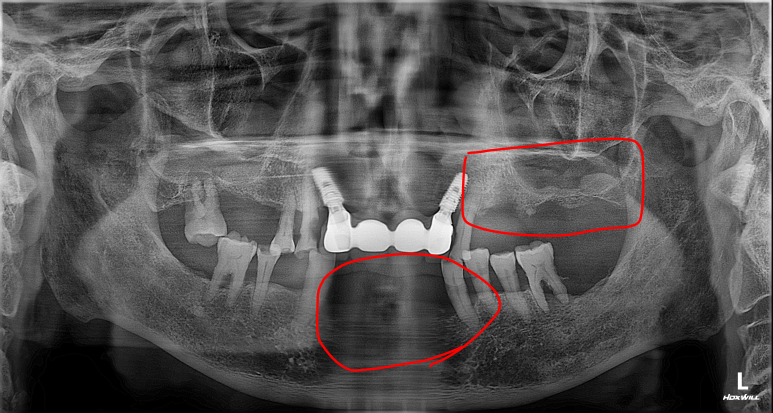

2025년 9월 11일 첫 내원 시 촬영한 파노라마 방사선 사진입니다.

진단 결과 하악(아래턱) 전치부 치아가 모두 상실되어 심미적인 문제는 물론, 앞니로 음식을 끊어 먹는 기본적인 저작 기능이 불가능한 상태였습니다. 또한 좌측 상악(위턱) 어금니 부위 역시 치아가 상실되어 있어 종합적인 보철 수복이 필요한 상황이었습니다.